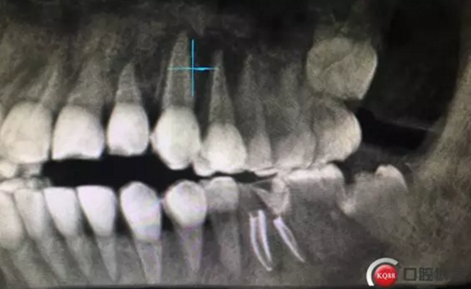

兩周后復(fù)診,完善根管治療,牙齦恢復(fù)良好,牙周探診深度最大2mm,未探及根分叉。

根管治療完成攝片

治療完成,聚羧酸鋅水門汀暫封觀察一周,后期常規(guī)根管樁全冠修復(fù)。同期16治療完成。